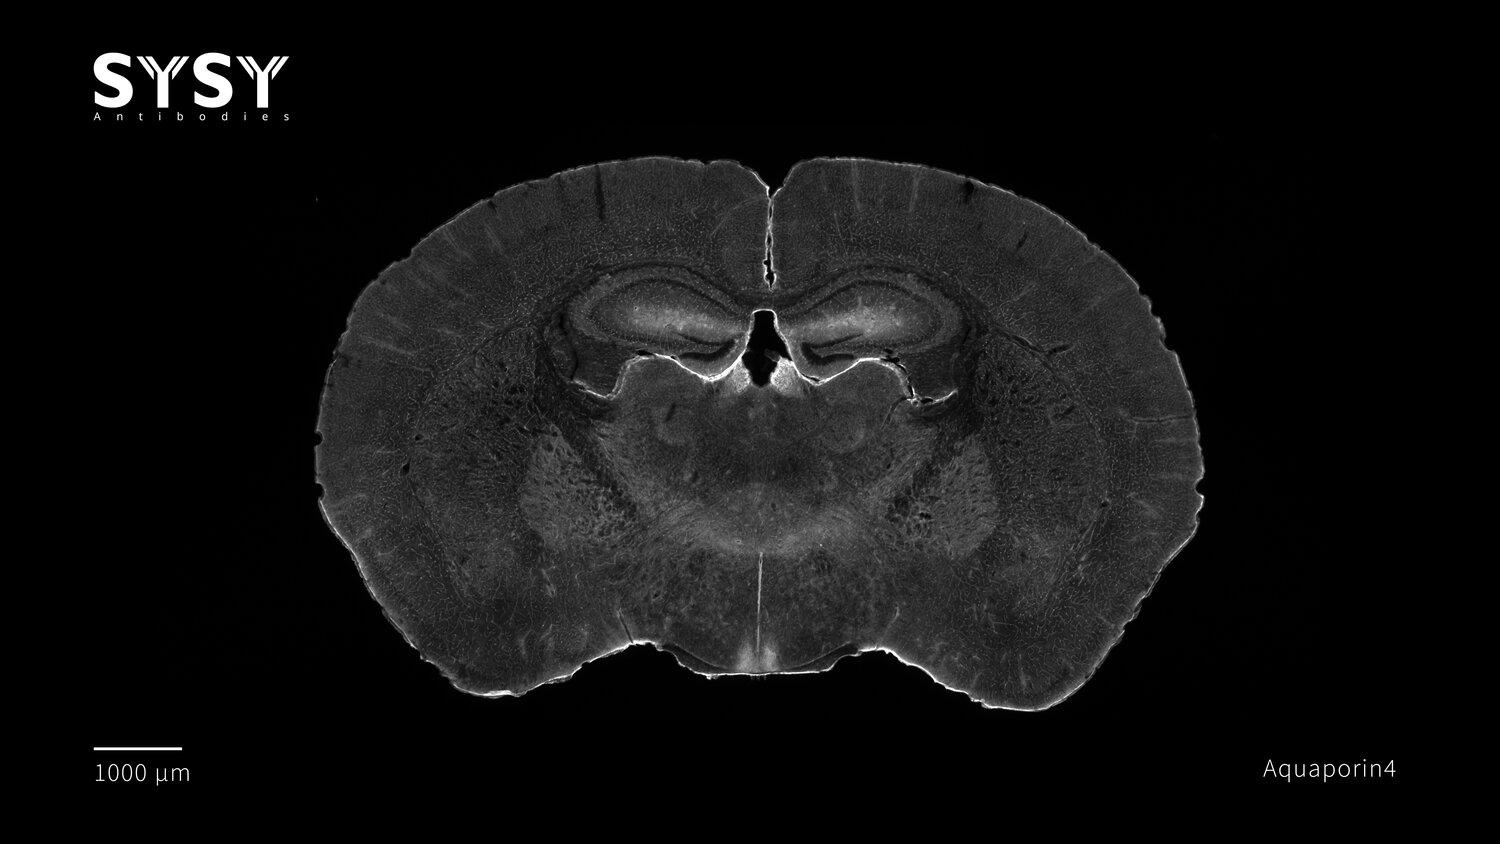

Aquaporin4

Indirect immunostaining of a formaldehyde fixed coronal mouse brain section with chicken anti-Aquaporin4 antibody (cat. no. 429 009, dilution 1 : 2000).